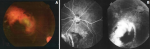

Résultats cliniques: l'examen clinique a retrouvé une acuité visuelle corrigée de 1/20 à droite (OD) et 10/10 à gauche (OG). Le segment antérieur était normal aux deux yeux, avec une pression intraoculaire (PIO) mesurée à 13 mm Hg de façon bilatérale. L'examen du fond d'œil droit a montré une masse solitaire, pigmentée, hétérochrome, ovoïde, en relief, d'environ trois diamètres papillaires, localisée en para-maculaire supérieure. Cette lésion refoulait l'arcade vasculaire rétinienne supérieure entourée d'un halo périlésionnel pâle évocateur d'une probable exsudation (Figure 1 A).

Démarche diagnostique: l'angiographie à la fluorescéine a montré une lésion hypo-fluorescente au temps précoce, devenant hyper-fluorescente au temps tardif, avec persistance d'un centre hypo-fluorescent (Figure 1 B). L'échographie oculaire (Figure 2) ainsi que l'imagerie par résonance magnétique (Figure 3) ont révélé une masse choroïdienne, saillante, en dôme ou en champignon, bien limitée para-maculaire supérieure, compatible avec une tumeur intraoculaire. Les caractéristiques qui ont été rapportés sont: masse tissulaire hyperéchogènes, hétérogène, de contours nets, hypervascularisée, siégeant à droite du nerf optique, mesurant 7x7 mm.

Figure 1: A) lésion hétérochrome; B) angiographie à la fluorescéine: lésion hypo-fluorescente au temps précoce et hyper-fluorescente au temps tardif